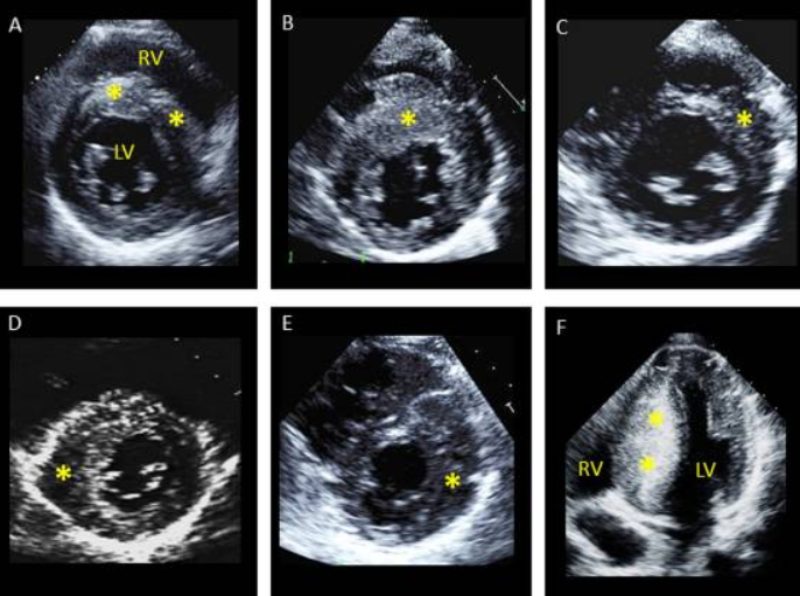

Hình ảnh siêu âm là một dữ liệu quan trọng trong việc chẩn đoán bệnh cơ tim phì đại và nhiều vấn đề tim mạch khác. Dưới đây là một số hình ảnh siêu âm thực tế.